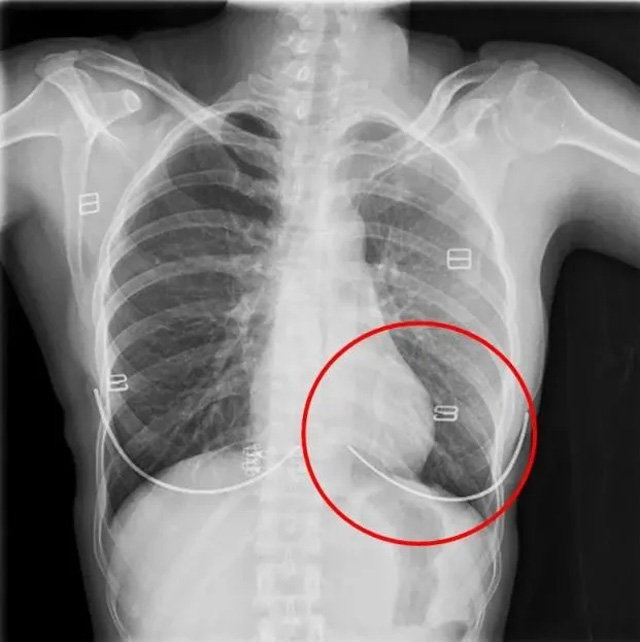

DR是一种比较常规的基础影像学检查方式,适用于人体各部位的健康普查及疾病检查等优势,在临床基础检查中备受医生和患者的青睐。DR体检车在健康体检中有着非常重要的地位,由通过电缆串接在一起的探测板、扫描控制器、系统控制及影像显示器等构成。对比CT检查而言,DR检查的价格更低,辐射剂量更小它可以让疾病预防,微细病变可更好显示诊断治疗提供科学的结果依据。很多外伤患者都要做DR检查,来判断是否骨折或其他的情况。体检过程中面对DR体检车做检查时候需要准备注意什么呢?很多时候大家都有这样的疑问,身上携带的物品是否会对图像造成遮挡或给机器带来干扰?检查前如何准备才不会影响检查准确性?